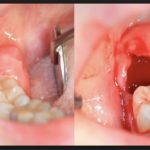

Если под капюшоном уже есть инфекция, боль становится пульсирующей, развивается флюс. В этой ситуации необходима помощь доктора, который произведет иссечение мягких тканей. Это безболезненная, быстрая операция, после которой больной почувствует себя лучше. После этого можно провести полноценный осмотр и решить, стоит ли удалять моляры. Также если лезет зуб мудрости, болит десна рядом и горло тоже першит, как при простуде, для облегчения симптомов прорезывания специалист делает «окошко» в мягких тканях, чтобы «восьмерка» быстрее вышла наружу.

- Поскольку, когда лезет зуб мудрости, десна опухает, стоматолог сначала убирает оттуда весь гной и обеззараживает рану. Далее специалист определяет положение моляра. Если он растет вверх, не затрагивает окружающие ткани, а проблема была только в нагноении, рекомендуется больше не проводить манипуляций.